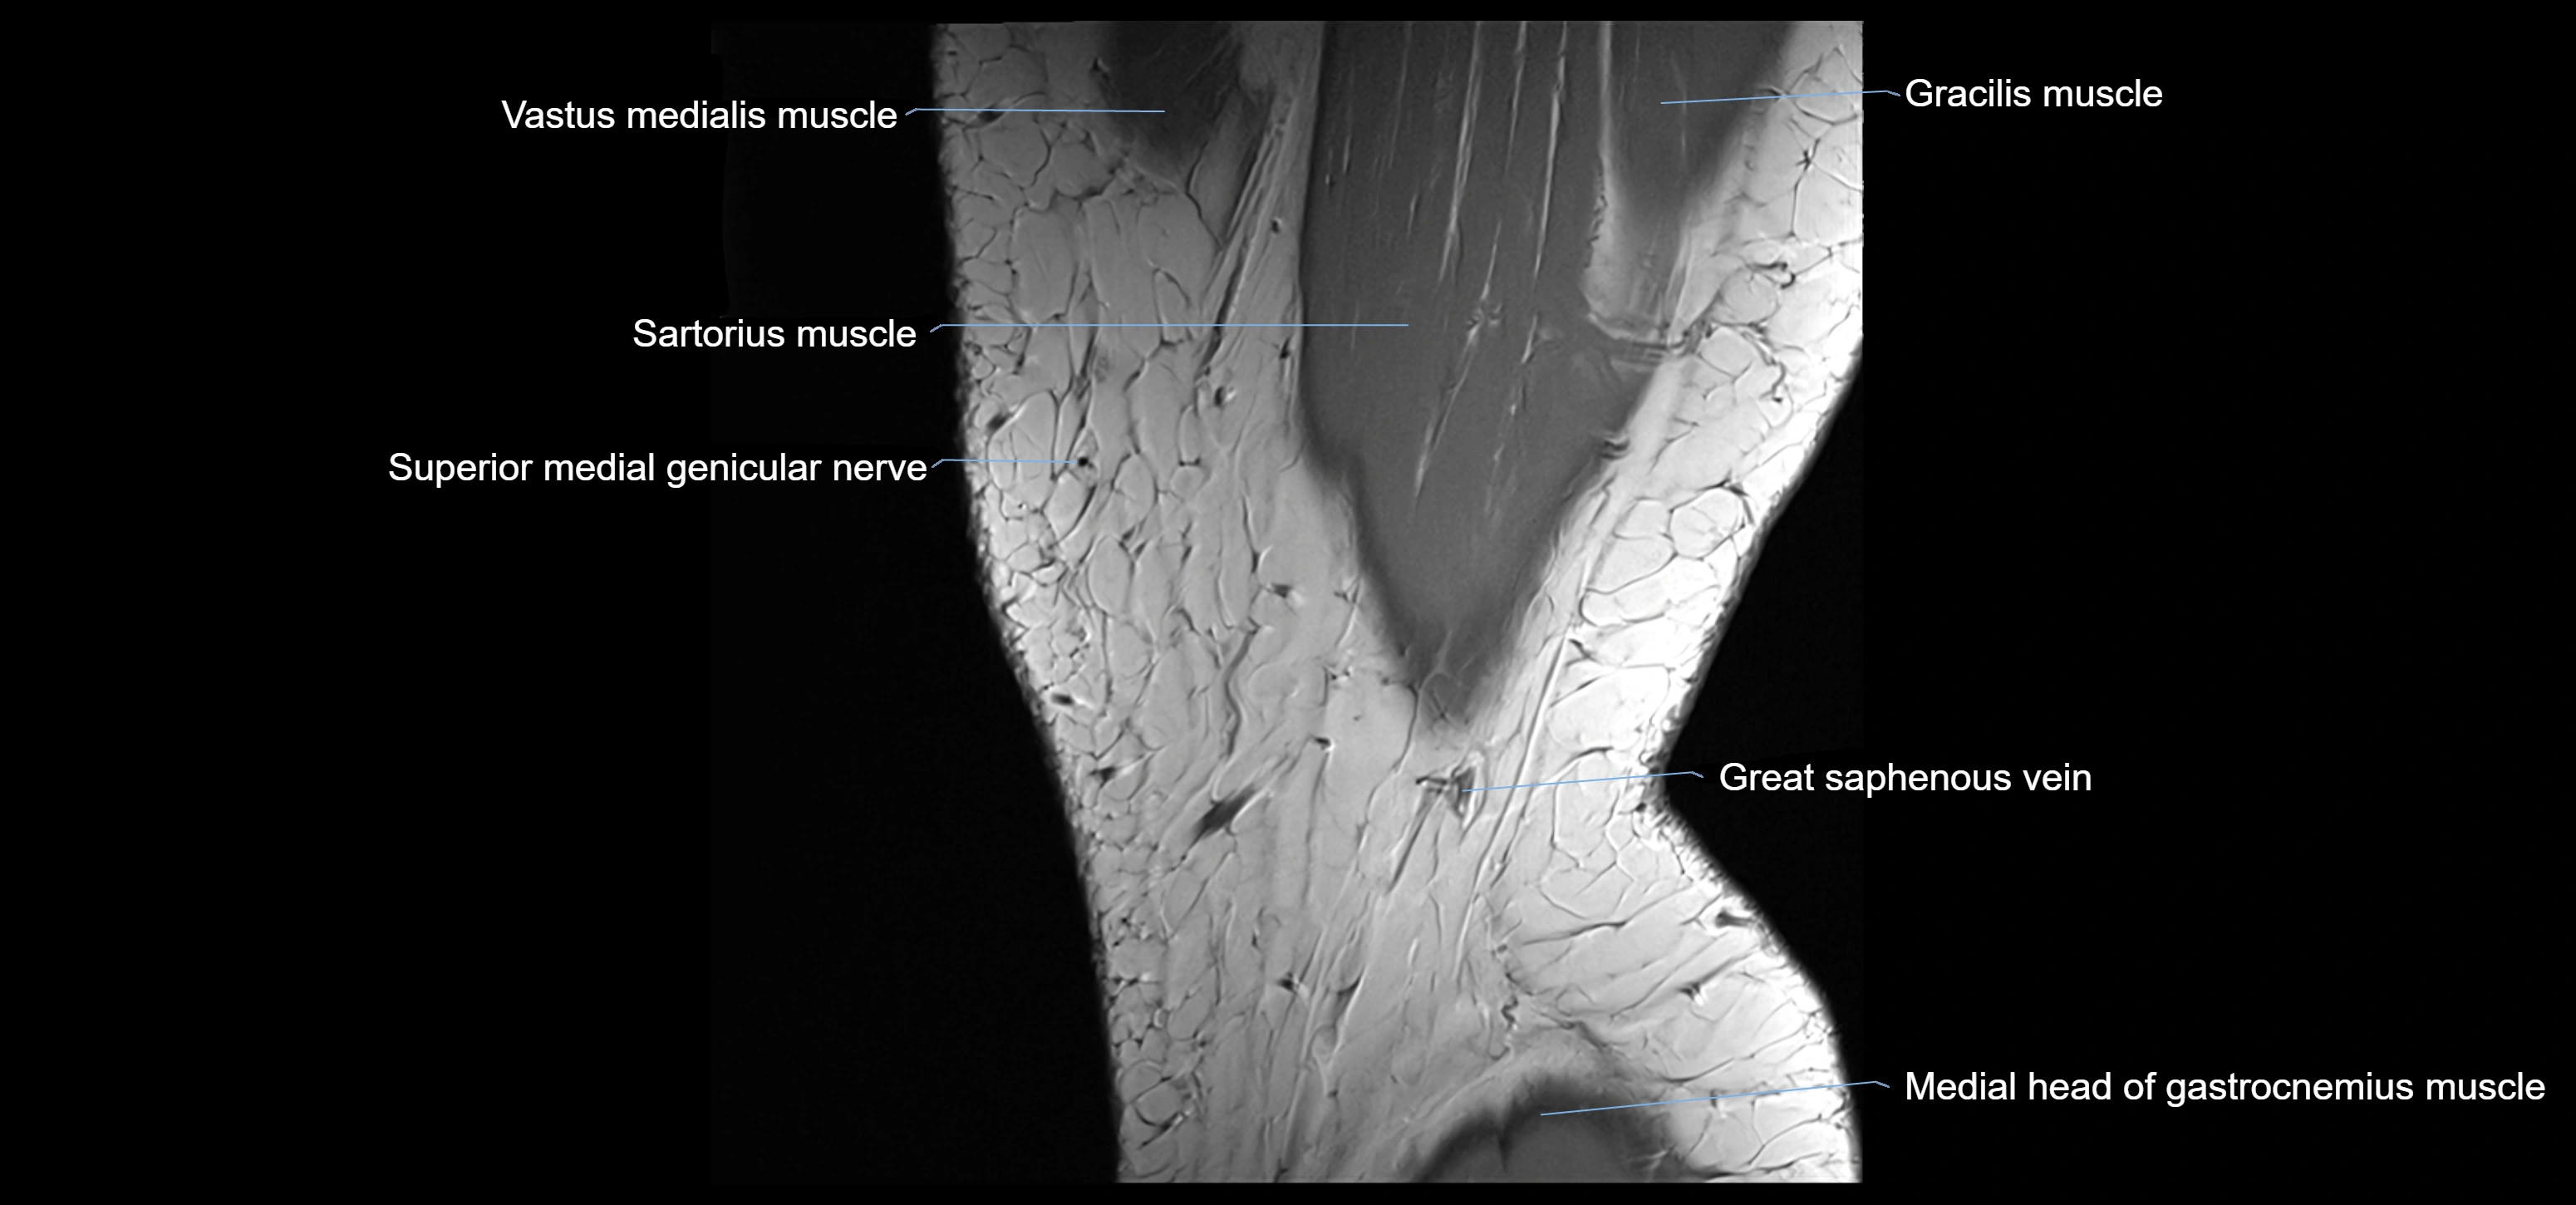

- Medial head of gastrocnemius muscle

- Saphenous nerve

- Sartorius muscle

- Vastus medialis muscle

- great saphenous vein